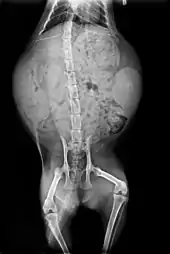

Skeleton

Cats have seven cervical vertebrae (as do most mammals); 13 thoracic vertebrae (humans have 12); seven lumbar vertebrae (humans have five); three sacral vertebrae (as do most mammals, but humans have five); and a variable number of caudal vertebrae in the tail (humans have only three to five vestigial caudal vertebrae, fused into an internal coccyx).[62]: 11 The extra lumbar and thoracic vertebrae account for the cat's spinal mobility and flexibility. Attached to the spine are 13 ribs, the shoulder, and the pelvis.[62]: 16 Unlike human arms, cat forelimbs are attached to the shoulder by free-floating clavicle bones which allow them to pass their body through any space into which they can fit their head.[63]